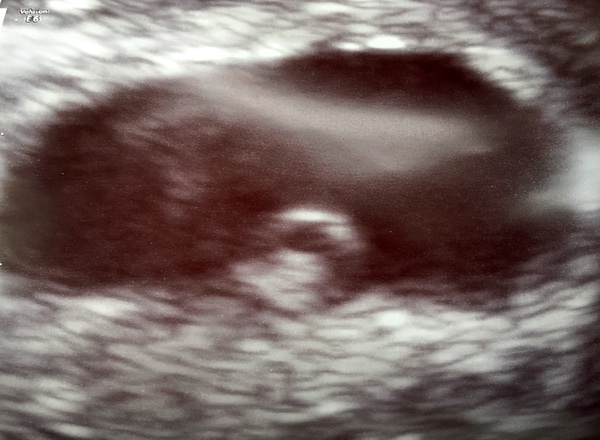

I was having abdominal pains so out of hours Dr referred me to EPU to check for etopic. Fortunately beanie is in the right place and they think the pain was from the ovulation cyst

Tabitha78 · 02/06/2016 19:03

This is what it looks like at the mo - little blob, yolk sac and then the big oval is the pregnancy sac.